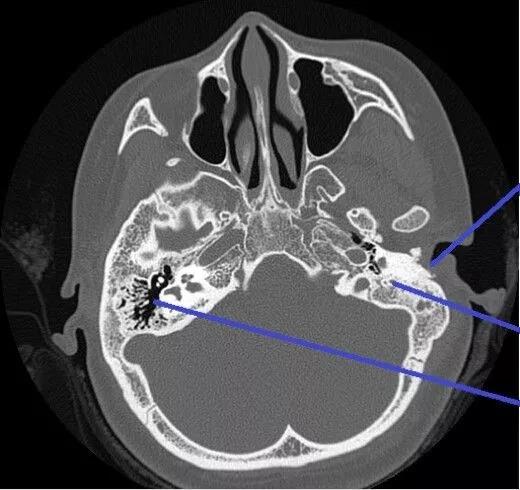

为了进一步明确病灶,我们做了CT检查,结果是这样的

CT检查可见左侧乳突气房密度增高,粘膜增厚,中耳鼓室内密度增高,粘膜增厚,左侧鼓膜增厚,听小骨结构大致正常,未见骨质破坏,考虑左侧慢性中耳炎。